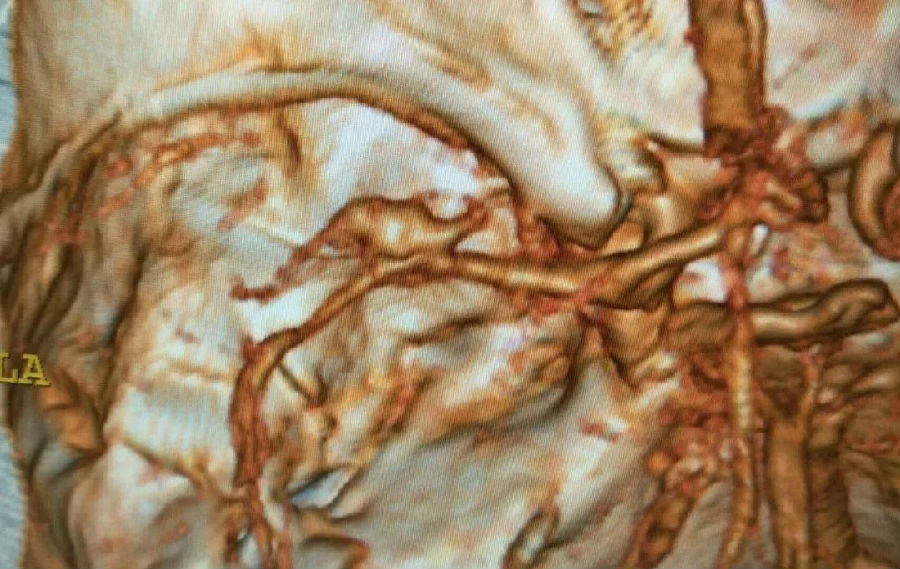

▲术前CTA显示右大脑中动脉动脉瘤

经64排CT血管造影进一步确诊,患者为颅内右外侧裂血肿,蛛网膜下出血。李要辉及时将造影显示的图像发给谭占国教授查看,远程接受治疗指导。

显微镜下,谭占国教授与多科医师分工协作,配合默契,小心翼翼解剖血管,抽丝剥茧,逐渐暴露位于M2处的动脉瘤。由于瘤颈较宽,采用临时夹阻断M1,用剥离子分离瘤颈两侧并放置一枚动脉瘤夹,夹闭瘤颈。最终,左侧颈内动脉、大脑中动脉近远端血流通畅。时间一分一秒的过去,经过5个小时努力,手术顺利结束。